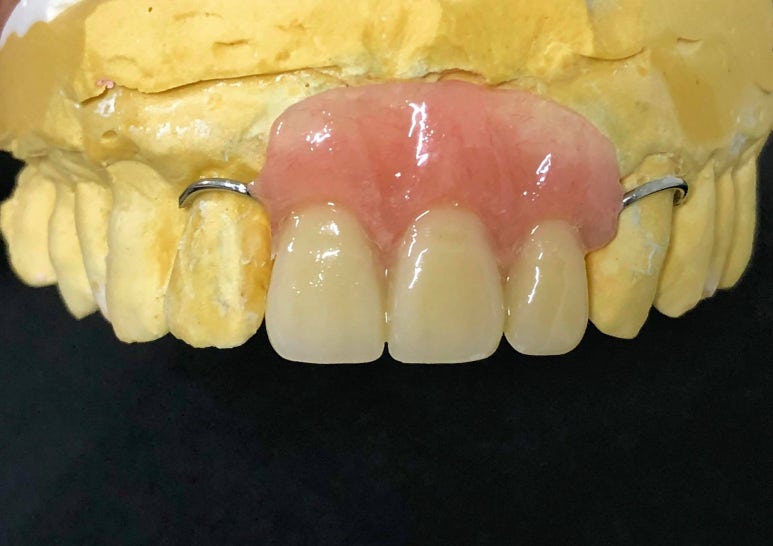

이때 저는 환자분의 심리적인 부담과

비용적인 고민을 조금이라도 덜어드리기 위해,

251023

앞니 4개를 발치하더라도

임플란트는 단 2대만 식립하는 계획을

제안해 드렸어요.

임플란트가 뼈와 굳는 2~3개월 동안

앞니가 없는 상태로 지내실 순 없기에,

뺏다 꼈다 하는

임시틀니를 제작해 드리는데요~

하지만 꼭! 기억하셔야 할 점이 있습니다.

임시 틀니는 사회생활을 위한

심미용 장치일 뿐이라는 점!

끼고 식사를 하시면 틀니가 깨질 수 있고,

무엇보다 잇몸 안의 임플란트를 눌러

치료가 실패할 위험이 있어요.

그러니, 식사하실 때는 반드시

빼두시는 것이 좋습니다.